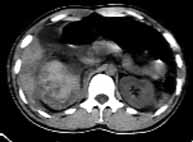

男性,22岁,车祸,被汽车方向盘压伤右季肋部,局部见长5cm的伤口。

ct表现:右侧肾上腺肿大,密度增高,右肾上极段肿胀,密度增高,右侧肾周间隙积血。

ct诊断:右肾及肾上腺挫裂伤